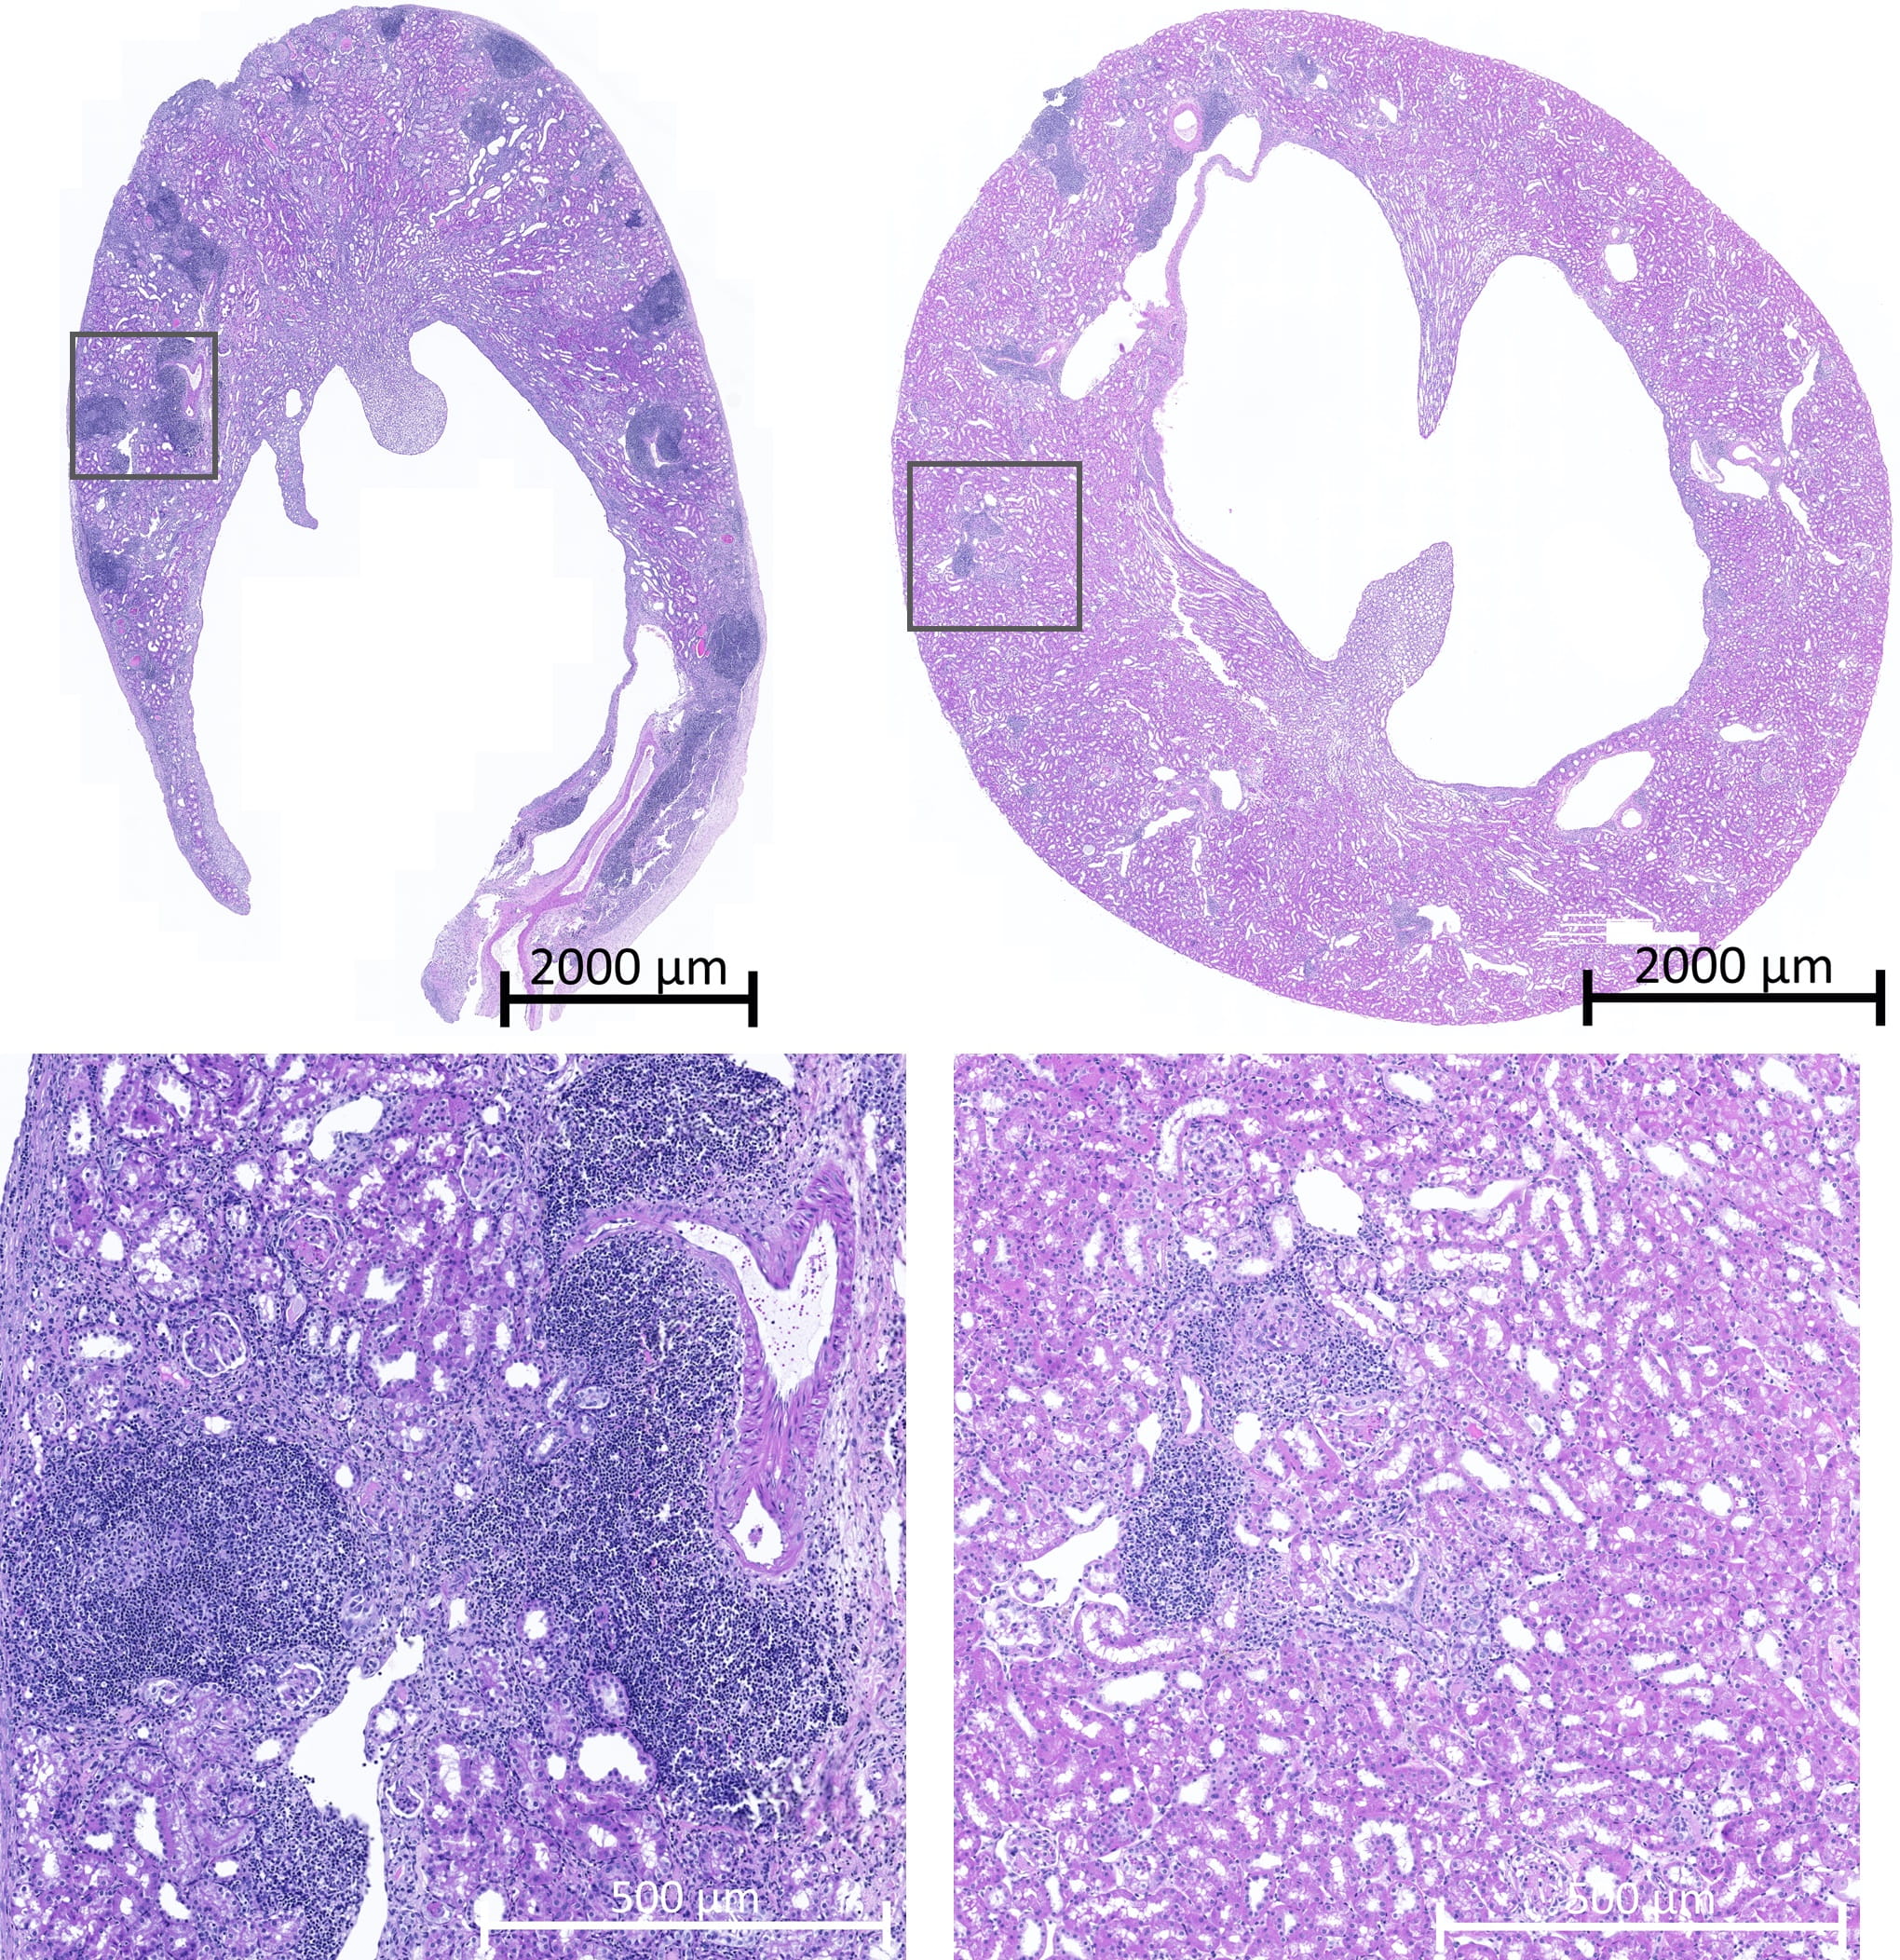

In the new study, researchers used a classical genetic ping approach to show that in mice a molecule called SIRP-alpha leads to innate immune system activation and differs between unrelated individuals. When the transplanted tissue SIRP-alpha is different from the host tissue SIRP-alpha, the transplant SIRP-alpha binds to a receptor called CD47 that is located on the recipient’s monocytes, a class of innate immune cells. This binding kicks off a series of cellular events that activate the innate and then eventually the adaptive immune system.

Blocking the interaction between SIRP-alpha and CD47 in mice prevented the monocyte activation, suggesting that disruption of this coupling could prevent recipient immune system activation. Future studies to examine how the interaction between SIRP-alpha and CD47 leads to monocyte activation could lead to new ways to prevent organ rejection.